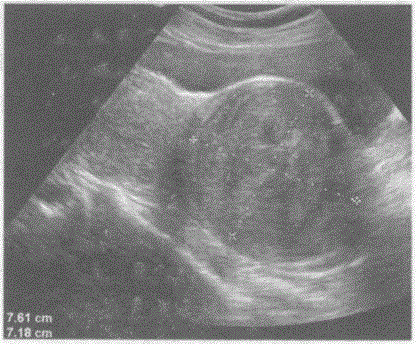

问题 临床资料:女,42岁,自述下腹坠胀,月经量增多3年余。 超声综合描述:子宫前位,宫颈部可见7.8cm×7.2cm低回声区,边界清晰,形态规则,内回声不均匀,呈漩涡状,向外突起,CDFI:周边可见少许血管绕行,呈动脉血流频谱。见下图及彩图105。 {图2} {图3} 超声提示:

选项 A.子宫颈妊娠 B.子宫颈肌瘤 C.子宫颈癌 D.阔韧带肌瘤

答案 B